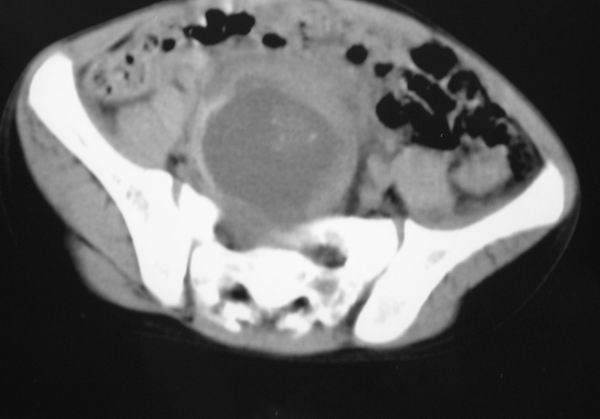

标题: PED0321:F 7 骶尾部肿瘤 有病理结果 [打印本页]

标题: PED0321:F 7 骶尾部肿瘤 有病理结果

骶尾部肿瘤 有病理结果

考虑畸胎瘤可能性大。骶尾骨无破坏。不考虑脊索瘤。

骶骨没有发现骨质破坏,畸胎瘤的可能性大